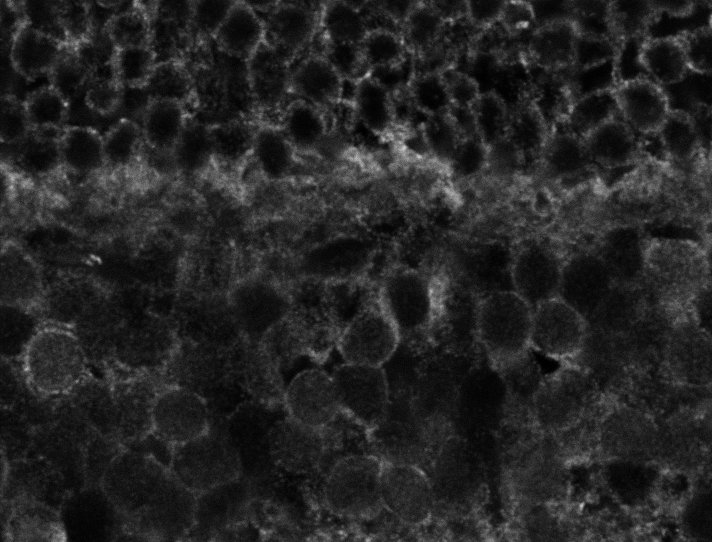

Healthy Retina

Healthy Choroid